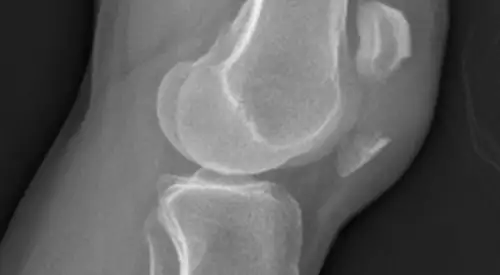

Las radiografías ayudarán a identificar la fractura de rótula.

En ocasiones se requiere la solicitud de pruebas complementarias (resonancia o TAC) para visualizar el estado del cartílago u observar con más detalle la fractura.